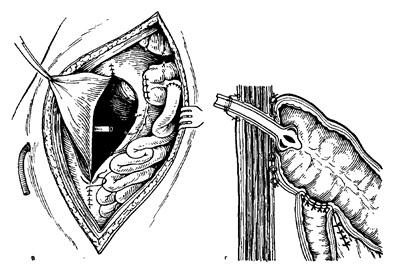

Ábra. 15. előírása ileotransverzoanastomoza CO-Heff oldalán.

és - alakítás a hátsó fal-ki; b - képező elülső fal; in - elvezetését Zabra busz-tér-sósav dréncső záródási rendellenességek hátsó parietális peritoneum:

g - a bevezetése a végén a cső a vastagbél bél kirakodás ana-stomoza.

Indikációk: 1) a rák jelenlétét a distalis vastagbélben az jelenségek a nem obstruktív tünetei peritonitis nélkül átjárhatóságát az általános nehéz a beteg állapotától anélkül, hogy a szál vypol radikális sebészetben. Ezekben az esetekben tsekostomiyu vagy vastagbélsipoly (proximálisan tumor) termelt, mint a minimális műtét bél mentesítés (vagy mint az első lépés a radikális műtétet hiányában metasztázis) 2) tsekostomiyu is szolgálnak a kirakodás a bél és a anastomosis a bal oldali gemikolekto-misszió, reszekció a szigmabélen fekélyek vagy más disztális vastagbél, amely kedvező feltételeket teremt yatnye-gyógyulás az anasztomózis, különösen, ha nem megfelelő a bél előkészítését a műtét.

Működés: váltakozó ferde rés a jobb alatti területet vzdoshnoy (mint a vakbél) származó krakkolt-niem aponeurosissal a külső ferde izomrostok nyersen elválasztjuk közötti belső ferde és keresztirányú izmokat, majd boncolgatni a hashártya kinyitják és a hasüregbe. Kivonat a vakbél elülső falán neki, amennyire csak lehetséges el kell távolítani a hasi seb és izolálja gézzel. Ha tsekostomiyu esetben oldott vészhelyzet-működés vastagbél obstrukció a kialakulását a típusú fistula tsekostomy Wietze la vagy Stamm - Kader, az elülső fal, a vakbél alkalmazott erszényes karakterlánc varrat átmérőjű 1,5-2 cm (16. ábra is.) . Vakbél fala központjában tasak nyitva van, és ez belsejébe vezetjük be egy vastag gumiból cső, amelynek átmérője 1,5 cm, ami egy catgutból varrattal összevarrjuk, hogy a szélén a nyílást a falon a bél (ábra. 16b). Ezután a segéd cső elmerül a lumenbe fal együtt beszegve, és a sebész megfeszíti a érkötőt varrat a cső körül, vagy a kapcsolt. A jobb tömítés a cső körül néha elő egy második érkötőt varrat, bizonyos távolságot 0,5-1 cm-re az első. Hashártya térhálósított folytonos-folyamatos vagy nodális catgutból megragadástól fali vakbél (ábra. 16 c) körül gumicső 1 cm-re, hogy (az első lehetőség), vagy vakbél varrt csomóponti selyem öltésekkel, hogy a parietális peritoneum a seb kerülete (második kiviteli ). Ezután ugyanezeket a szálak varrt a széleit a bőrsérülések vakbél fal körül a gumi cső (1 cm-re ez).

Ábra. 16. Tsekostomiya. Ez NN-művelet.

és - kivetése erszényes-karakterlánc varrat az első fal a vakbél;

b - bélfal nyitó erszényes-karakterlánc varrat a központban, és bevezetése lumenébe egy vastag gumicső jajgat bélben, amely varrt a nyílás széle a bélben; a - merítés a gumicső a érkötőt varrattal varrás bryushi HN következik megragadása fali sing-körül cső belekben.

A sebet összevarrtuk a rétegeket, amíg szegett vakbél. A két hálószobás oldalsó szálak bőr varrás mindkét oldalon erősen kötődik az alján a csőbe úgy, hogy nem esik ki a bélrendszerben. A külső része gumicső növekvő széles kanül cső azonos átmérőjű-ra. A végén a cső merítjük egy korsó oldattal klór-on, felfüggesztették a beteg ágya.